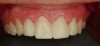

Fig 15. Diagnostic wax-up for porcelain veneers teeth Nos. 6 through 11.

Figure 15

Fig 16. VPS tooth preparation template fabricated on diagnostic wax-up cast. VPS template is cut with a scalpel at the incisal edges of the anterior teeth.

Figure 16

Fig 17. VPS reduction/preparation guide placed to evaluate the preparations needed for fabrication of the porcelain veneers for teeth Nos. 6 through 11.

Figure 17